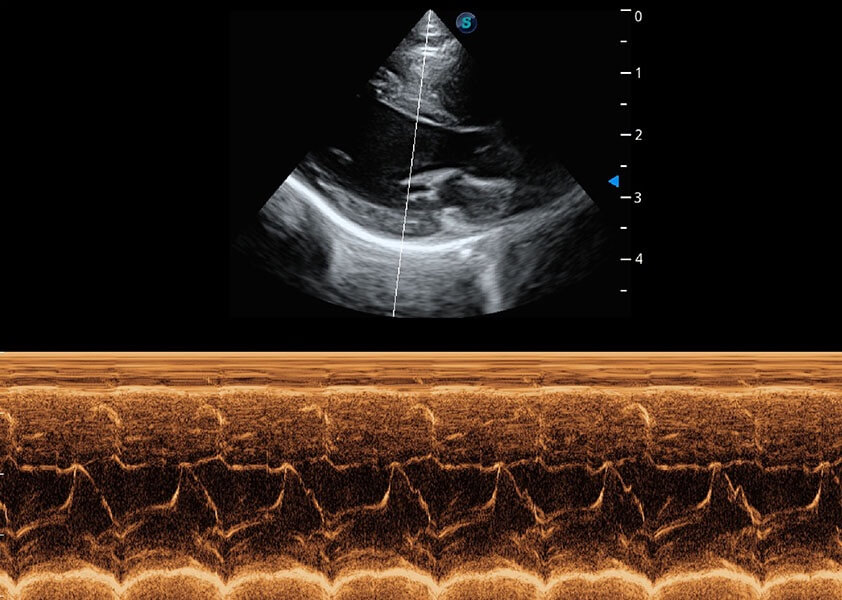

ProPet 60 作为一款高端台式动物超声设备,为动物医生的日常诊断提供了一系列贴合动物临床需求、解决临床实际问题的高级成像功能。凭借全系列高清探头,满足医生对腹部、心脏、生殖、浅表、肌骨等成像的所有需求,切实帮助您提升检查效率,提高诊断信心。

动物是人类最亲密的朋友和最值得信赖的伙伴。玖鼎集团也一直致力于探索动物专用的超声影像解决方案。 全新推出的ProPet系列,是玖鼎集团在动物超声影像智能化、专业化、精准化的一次跨越式革新。动物不能用言语来表述自己的不适,通过超声影像,ProPet系列搭建了动物医生与不同物种沟通的“桥梁”,为动物医生注入了“治愈之力”。